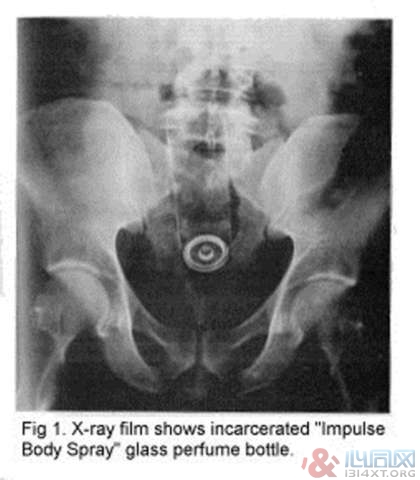

5. 一瓶香水